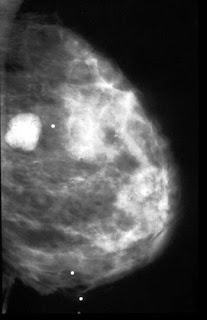

- BI-RADS 2 =Benign Finding:Like BI-RADS 1, this is a normal assessment, but here, the interpreter chooses to describe a benign finding in the mammography report.

Radiologist is still concluding that there is no mammographic evidence of malignancy.

Category 2=secretory calcification

Category 2 =fibroadenoma

Category 2 =vascular calcification

Category 2 =round calcification